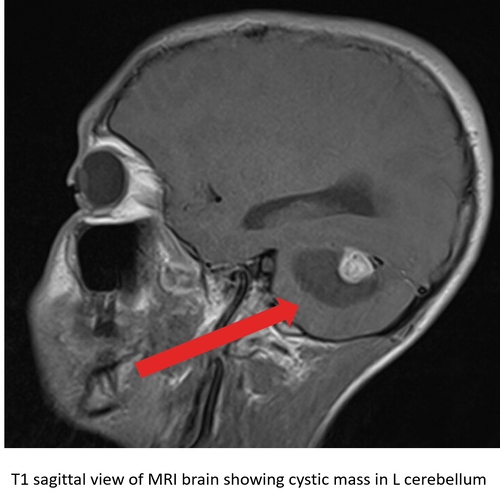

| Don't Worry, It's All In Your Head! - Page #3 | |||